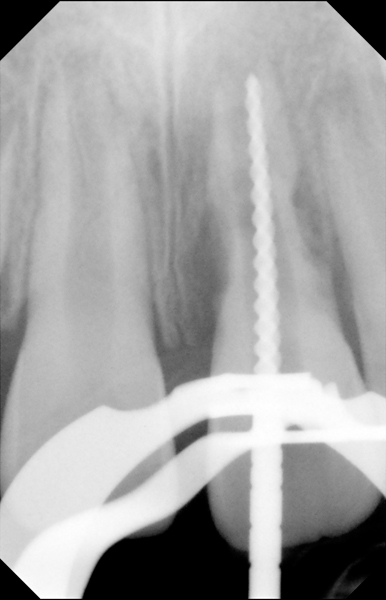

Clinical procedure: Regeneration of the endodontic pulp space is indicated for cases with very thin dentinal walls and an open apex that is more than 1 mm in diameter radiographically (Figure 4). Disinfection of the root canal system is performed using sodium hypochlorite irrigation followed by a triple antibiotic paste dressing that is left in place for 1 week. At the second visit, ethylenediaminetetraacetic acid (EDTA) is used to condition the dentin walls, which results in the release of growth factors, and bleeding is stimulated in the periapical tissues (where stem cells are located), with the aim of filling the pulp space with a stable blood clot, which would serve as the scaffold. MTA is then placed at the canal orifice in contact with the clot to protect it from coronal microleakage (Figure 5 and Figure 6). In time, the clot should be replaced with a reparative tissue of variable composition, and the root walls should continue to thicken due to the deposition of a dentin-like material on the pre-existing root dentin27,28 (Figure 7 and Figure 8).

Fig 5. Working length confirmation.

Figure 5